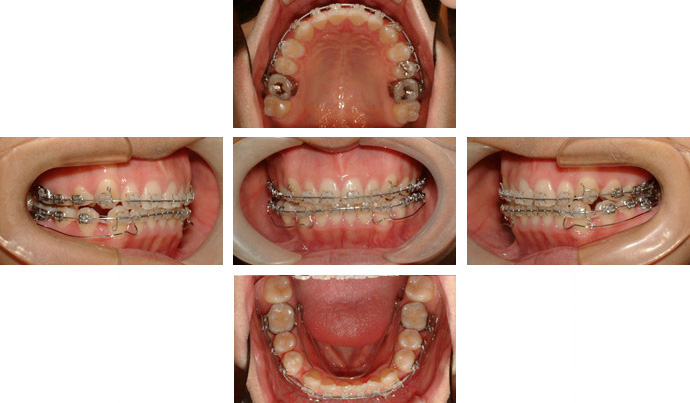

歯列を横方向へ拡大する装置、QH(クォードヘリックス)、BH(バイヘリックス)とダイレクトボンディング法でマルチブラケットを装着し治療を行った。

<治療前>

<治療中>

<治療後>